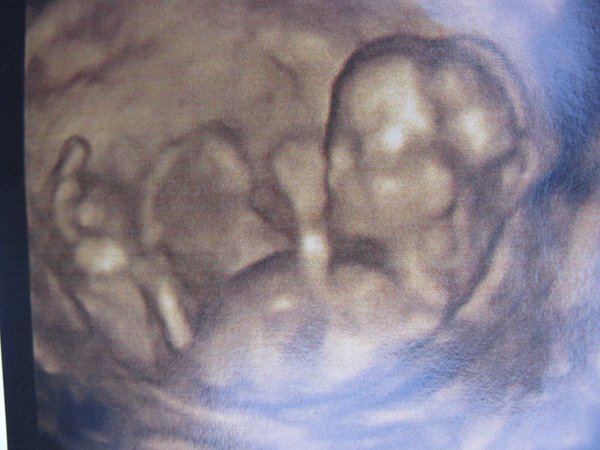

Én is itt vagyok, de nagyon elkeserdve. Annyira depis voltam az integrált óta, hogy nem is volt lelkierőm írni. A babával minden okés, 80 % hogy kislány (amit szeretnénk is), tarkóredő 1,4, szóval minden tökéletes lenne,

de annyira alul tapadt meg a méhlepény, hogy már most eléri a belső méhszájat. Aug. 6-án vissza kell mennem és akkor kiderül hogy mi lesz a sorsom, de ha ránő a méhszájra akkor azt mondta a doki, hogy szigorú fekvés, mert vérzés lehet és az viszont olyan veszélyes hogy el is vérezhetek, és bármi vérzés kezdődik azonnal rohanni kell a kórházba.